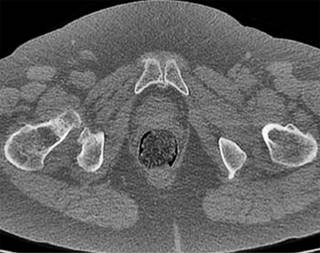

Posteriormente se solicitó una tomografía computarizada (TC) de pelvis en el que se confirmaban los cambios degenerativos (Figuras 4 y 5) y una resonancia magnética que mostraba hallazgos de inflamación en las sínfisis compatibles con osteítis de pubis, asociados a edema de la musculatura adyacente. Ambas pacientes estuvieron realizando sesiones de fisioterapia y toma de antiinflamatorios no esteroideos (AINE) y corticoides con escasa mejoría. La infiltración de bupivacaina junto con corticoide fue el tratamiento más efectivo, pero pasados los dos meses la clínica, se reprodujo y se planteó en ese momento la opción quirúrgica. Las puntuaciones en la escala visual analógica (EVA) previamente a la cirugía fueron de 8 y 9, respectivamente.

Figura 5: Tomografía computarizada corte axial: misma paciente en la que se aprecia osteofito medial.